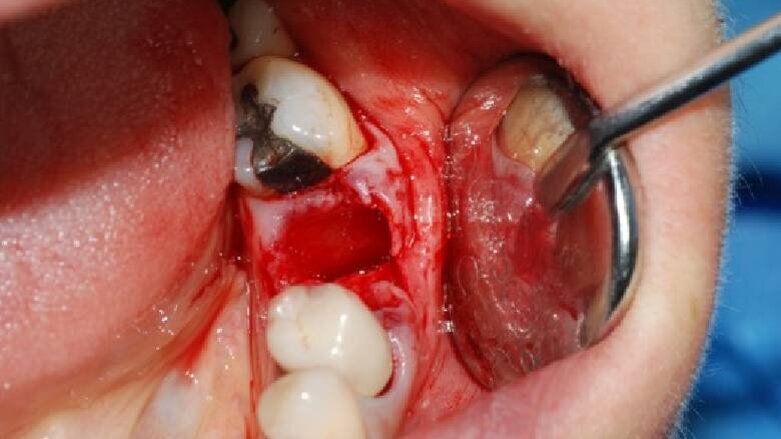

Dopo l’anestesia locale, è stato scollato un lembo a spessore totale e il dente estratto in modo atraumatico (Fig. 1). Successivamente, l’alveolo post-estrattivo è stato zeppato con granuli di osso bovino decellularizzato (Re-Bone®, Ubgen, Padova/Italy) e utilizzata una membrana di pericardio bovino come barriera (Shelter® Membrane, Ubgen, Padova/Italy) (Fig. 2).